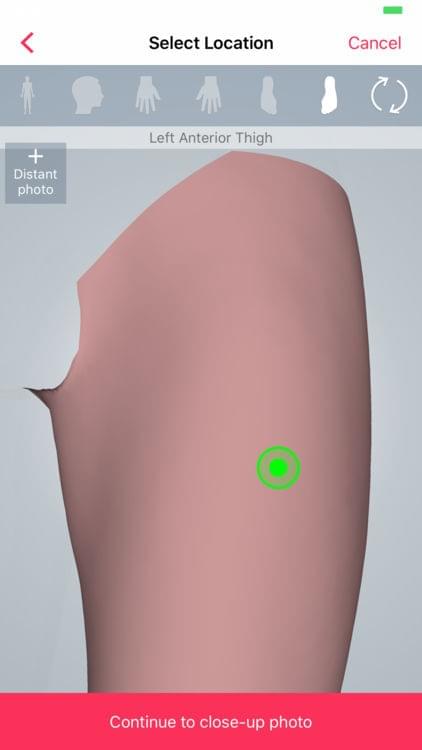

Skin — Anatomic Mapping

Skin is a digital health imaging app for tracking of moles and skin lesions. The platform is targeted towards academic researchers, physicians and patients looking to integrate a robust sharing platform for the management and surveillance of dermatological conditions. This app gives medical institutions and physicians a secure option to create scalable studies with hundreds of patient participants. The tool is intended to help support the creation of an intelligent model for the accurate diagnosis of skin diseases.